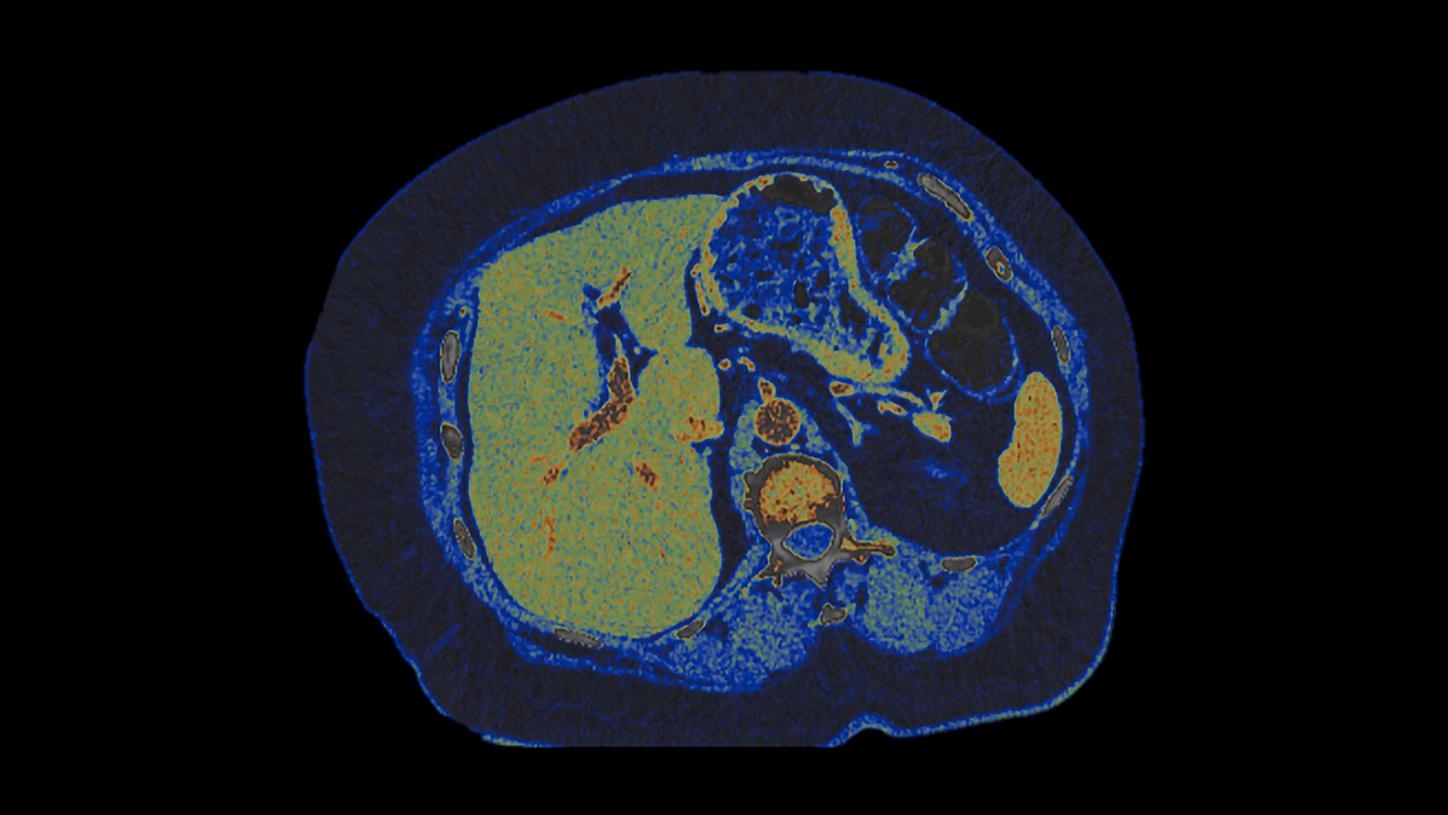

At the heart of NAEOTOM Alpha® is a radically new photon-counting detector. The QuantaMax detector directly converts X-rays into an electrical signal, which is then used to create an image. The energy of each X-ray is measured, so spectral information is available for every scan, and the images are contrast-rich with high spatial resolution at the same dose. Combining the high spatial resolution of the QuantaMax photon-counting detector with our Dual Source temporal resolution enables the visualization of fine details for increased diagnostic confidence.